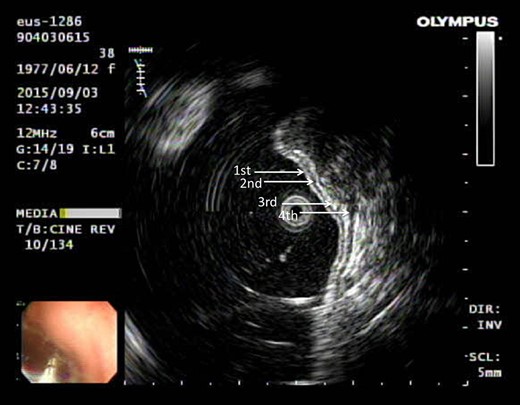

This is a 38-year-old female without any underline disease who came to our out-patient department due to a 2-month history of intermittent abdominal fullness and distension sensations. At first, she visited our gastroenterologist where medications promoting bowel motilities were prescribed but in vain. To further assess her condition, endoscopic ultrasonography was arranged which revealed a hypoechoic tumor with a diameter of 21.3 mm arising from the fourth layer of gastric wall. (Figs 1 and 2) An endoscopic biopsy was performed but reported negative findings due to failure in acquiring submucosal specimens on that biopsy. Based on epidemiology, gastrointestinal stromal tumor was suspected. Computed tomography was then arranged (Fig. 3) which revealed a submucosal tumor with heterogenous enhancement posterior wall of gastric antrum. No other lesion was found during that examination. Under such findings, she was then referred to a gastrointestinal surgeon for further surgical intervention.

Ultrasonography showing tumor arising from the fourth layer of the gastric wall.

Gastrointestinal stromal tumor (GIST) under ultrasonography also shares similar feature by arising from the fourth layer of the gastric wall.